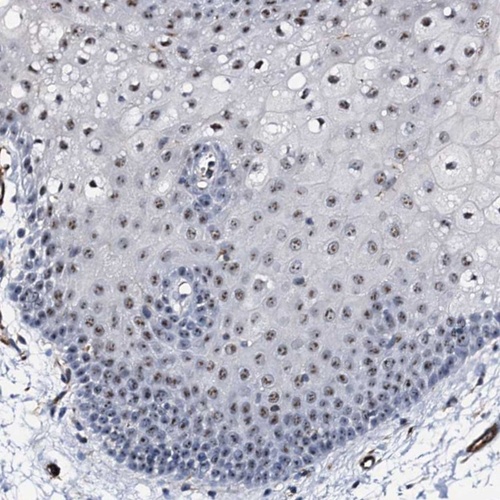

Immunohistochemical staining of human oral mucosa shows moderate nucleolar positivity in squamous epithelial cells.